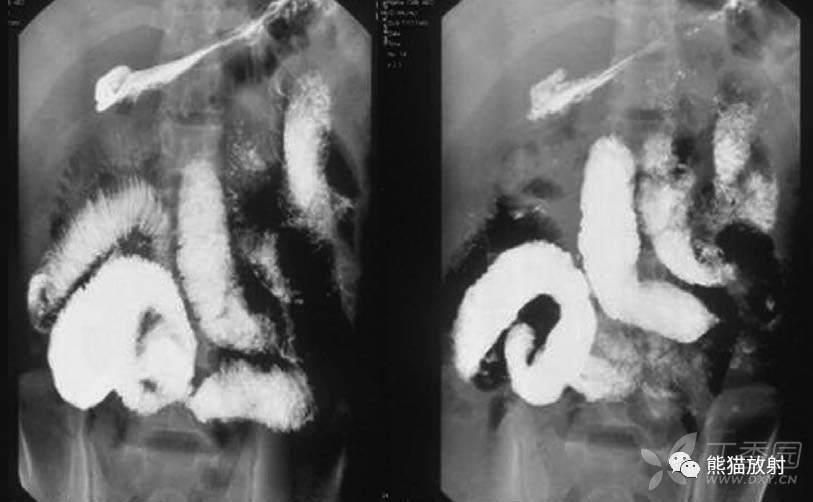

小肠钡剂通过迅速,部分小肠形态固定。

早期肠结核可见粘膜不规则和毛刺样改变。

多发性小肠狭窄伴部分扩张

小肠狭窄与扩张并存,形态固定,小肠粘膜增厚。